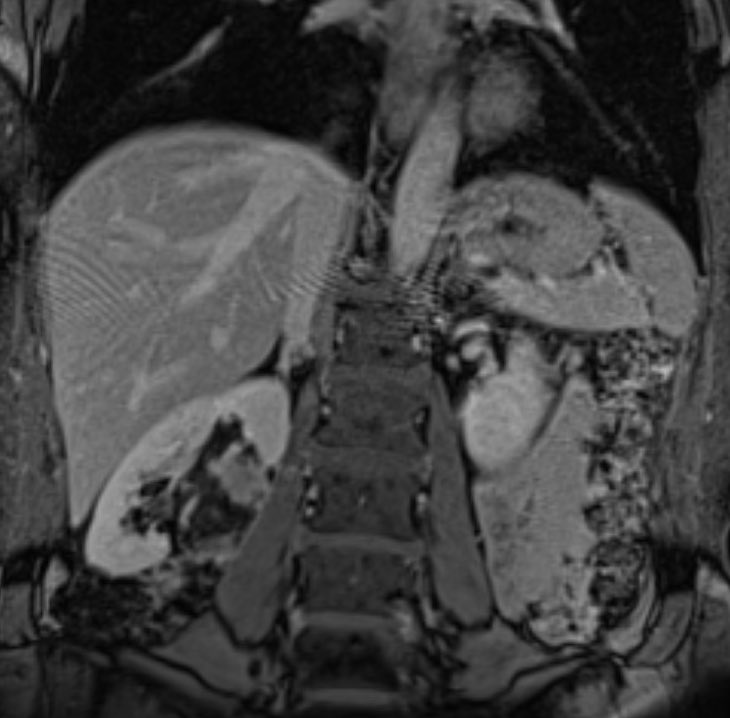

David Léon MD@IdCathThat·

Successful PVR-TIPS! Coronal CT and Trans-splenic access venogram showing chronically thrombosed portal vein. TIPS was placed using standard gun sight technique! @SIRRFS @SIR_ECS

David Léon MD tweet mediaDavid Léon MD tweet mediaDavid Léon MD tweet mediaDavid Léon MD tweet media

English